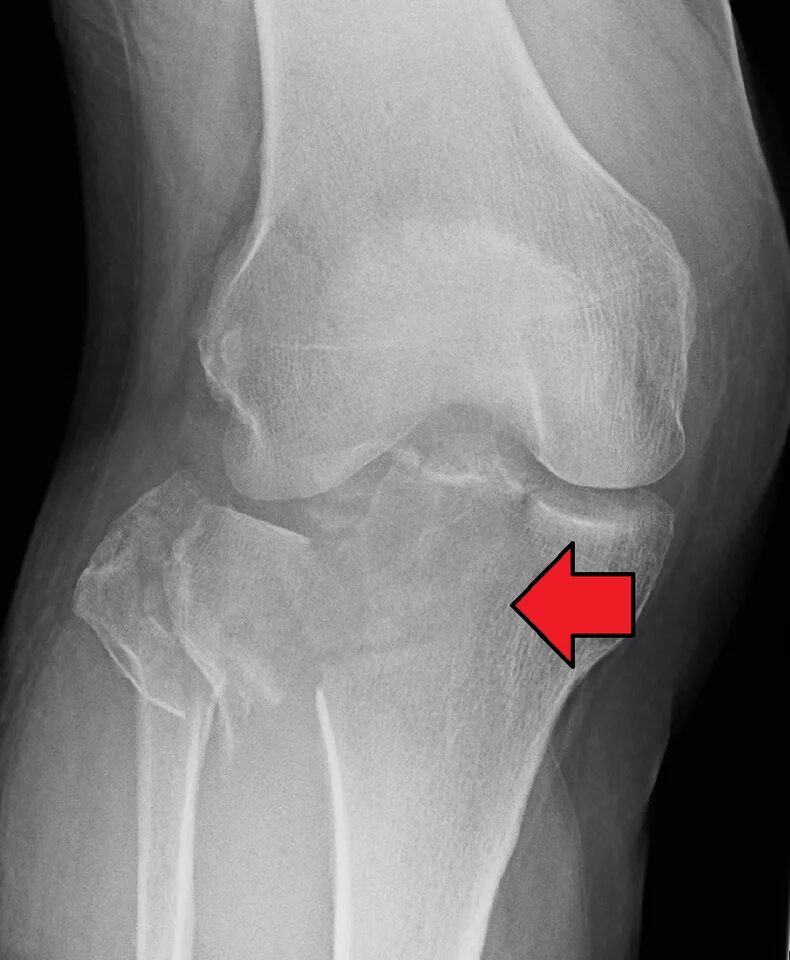

Перелом коленного сустава мкб